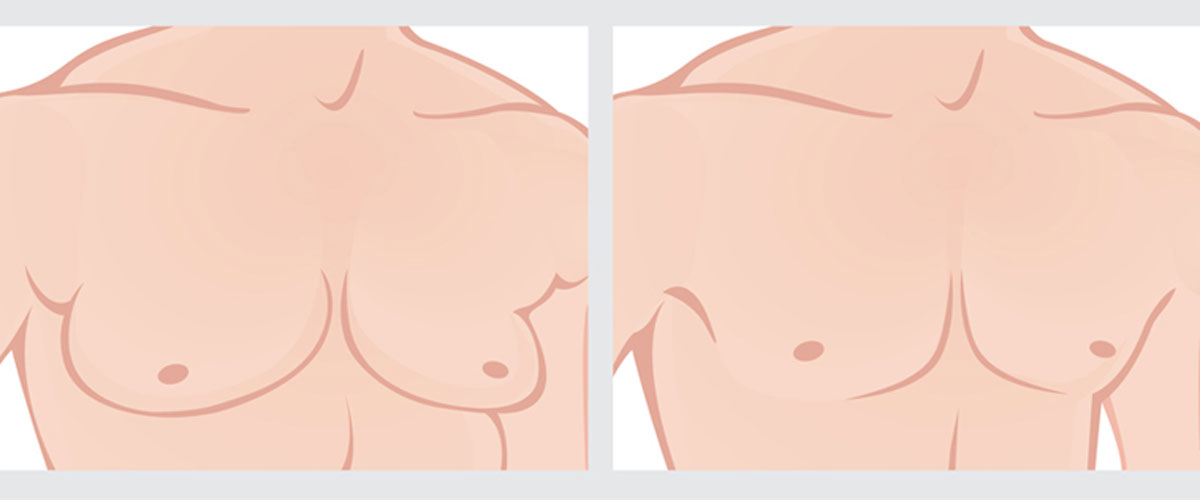

Gynecomastia Surgery

In some cases, gynecomastia has a shelf life and can go away on its own. Particularly in the cases of pubescent males who are going through standard hormonal imbalances affecting their age group. Once the hormones even out—something that can usually takes 6 to 12 months—the symptoms of gynecomastia can disappear on their own, providing a great sense of relief for the patient. In some cases however, the cause of gynecomastia remains unknown and it does not naturally resolve itself. As a result, surgery can be a good option to alleviate the difficulty of living with this condition.

Surgery is not a decision to be taken lightly. But if you have consulted your doctor and tried all other options available, then it can bring a great sense of relief while ridding you of the physical and psychological discomfort that comes with gynecomastia.

Surgery consists of the removal of tissue from the breast area and in most cases requires a general anesthetic (although in some cases it can be performed with a local anesthetic and some form of sedation).

There are two types of tissue that exist in men’s breast, the fatty tissue and the more firm tissue. If the gynecomastia a result of just the fatty tissue, then often a liposuction can be performed to realign the size of the breasts.

If the gynecomastia requires removal of the more firm tissue in the breast then the tissue will not be able to sucked out and will need to be cut out with a traditional scalpel.

Sometimes patients will need both liposuction and a traditional removal of tissue to obtain their desired result. It’s best to ask your doctor which option will work best for you.

The main physical symptom of gynecomastia is extra tissue in the breast area. Some of this can be softer tissue and some of it can be harder. In most cases the area is not painful but can be tender to the touch. Similar to women’s breast when menstruating or pregnant.